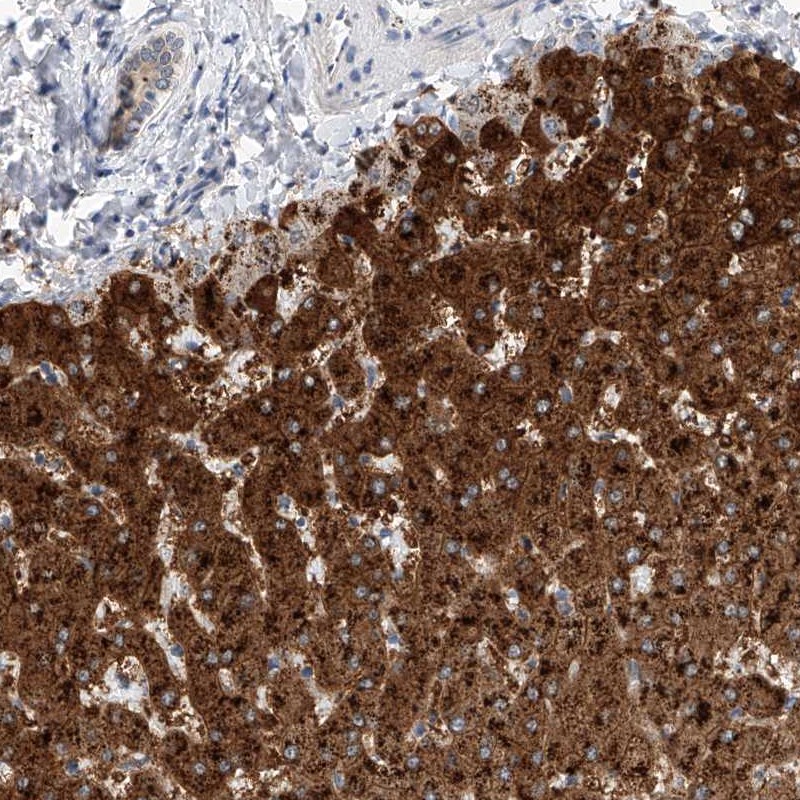

Immunohistochemical staining of human liver shows strong granular cytoplasmic positivity in hepatocytes.